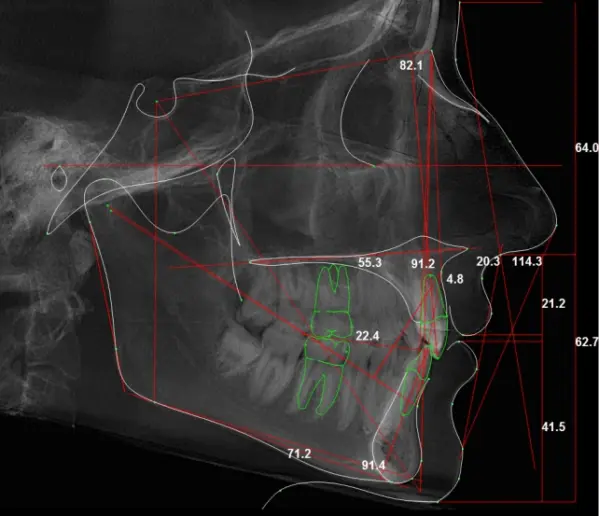

На начальном этапе работы мы объединили наши знания в области медицины, математики и программирования. Подумали и предложили ребятам из «Медилайт» программу, которая самостоятельно будет проставлять на рентген-снимке ключевые точки и подсчитывать углы, необходимые для расчета ТРГ и дальнейшего определения диагноза пациента. По итогам диагностики сервис будет выводить все получившиеся значения на итоговый снимок.

Суть функционала сервиса заключается в следующем: алгоритмы программы определяют ключевые точки на рентгеновском снимке, после чего врач выбирает методику анализа и расчета ТРГ. Согласно выбранной методике, программа автоматически вычисляет углы отклонения и предоставляет результат в едином документе. Это позволяет врачам установить пациенту точный диагноз на основе полученных данных.